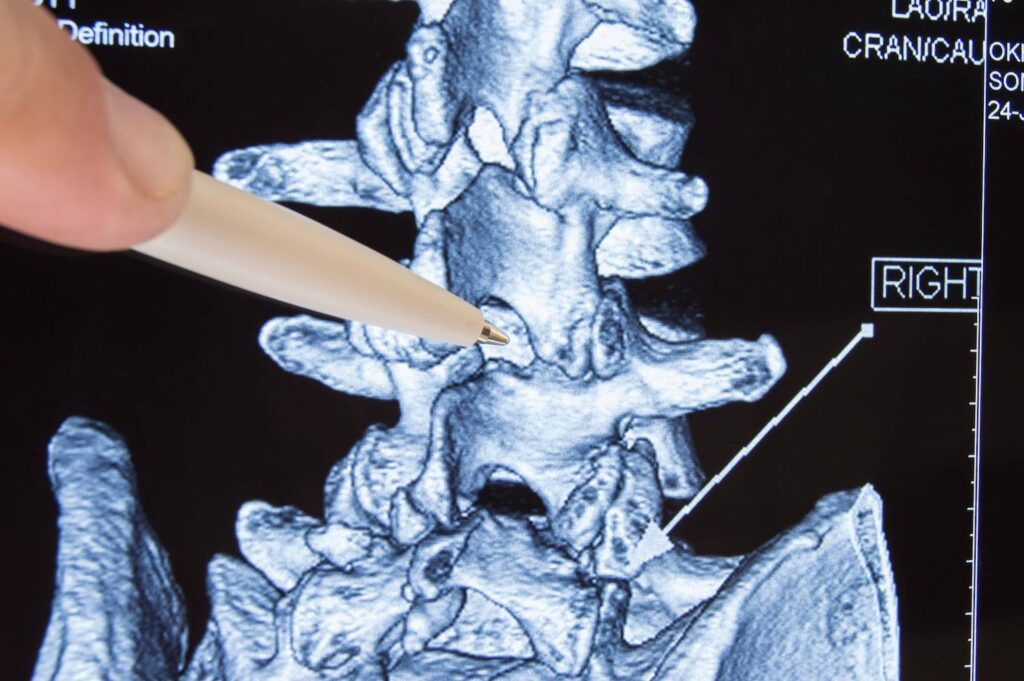

Nach der körperlichen Untersuchung kann der Arzt die Diagnose mit Hilfe von bildgebenden Verfahren wie Röntgenaufnahmen, CT-Scans oder MRT-Scans bestätigen. Es gibt auch Fälle, in denen ein Arzt einen Nervenleitungstest oder eine Elektromyographie durchführen kann, um zu prüfen, ob die Nervenwurzel geschädigt ist. Die häufigste bildgebende Untersuchung zur Diagnose der Erkrankung ist die MRT, die detaillierte Bilder der Weichteile im unteren Rücken liefert.

Die MRT-Untersuchung kann mit einem in die Blutbahn injizierten Kontrastmittel durchgeführt werden, aber das ist nicht immer der Fall. Mit dem Test kann festgestellt werden, welche Bandscheibe betroffen ist, wenn es eine Nervenkompression gibt. Mit dem MRT-Scan können auch Rückenmarkstumore, Abszesse und knöcherne Überwucherungen erkannt werden.